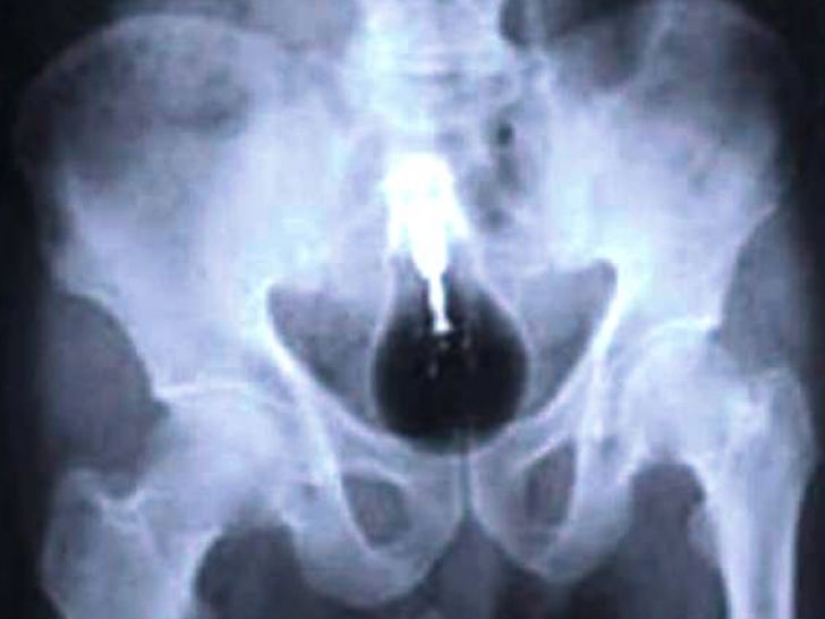

Many men want to be romantic and make an offer to their half in some unusual way. And many people use, for example, food to hide a surprise in the form of a ring there. So, men, make an offer before your betrothed decides to try this dish with a surprise.